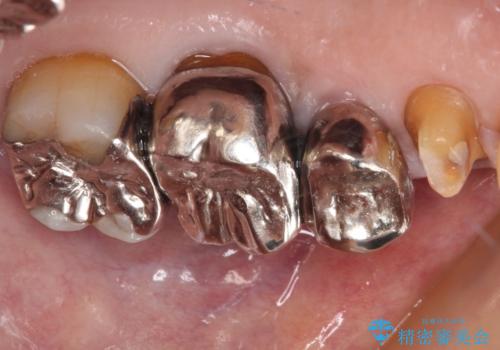

- 詰め物が欠けてしまい、虫歯かもしれないから診てほしいとのことで来院された患者様です。

精査の結果、詰め物の下に虫歯が大きく広がっているのがわかりました。

虫歯の範囲が大きく、部分的な詰め物では対応が難しいため、オールセラミッククラウンにて補綴することとしました。